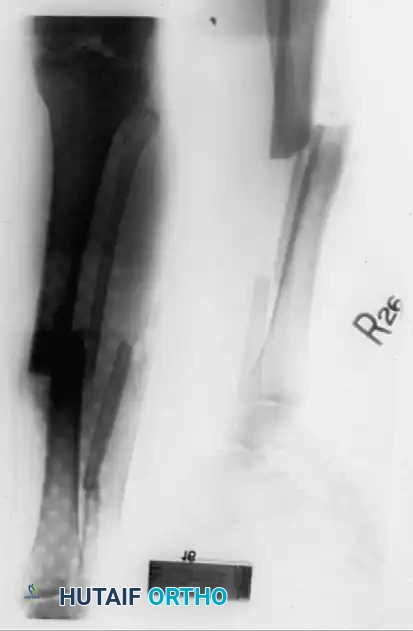

Advanced Frame Application and Bone Transport

The Ilizarov method allows for the simultaneous correction of angular, rotary, and translational deformities alongside lengthening. Deformities of 10 to 15 degrees can often be corrected acutely during frame application; larger deformities must be corrected gradually using hinges and motors to prevent neurovascular compromise.

When managing segmental bone loss, the leading edge of the transported bone fragment (the "docking site") frequently becomes covered in fibrous tissue during its journey. Upon arrival at the principal fragment, this docking site usually requires surgical freshening, decortication, and the addition of autogenous bone graft to ensure a solid bony union.

The sequence of correction for complex deformities varies, but a fundamental rule is that limb length must generally be reestablished before severe angular or translational deformities are fully corrected, as premature correction can tether neurovascular structures.